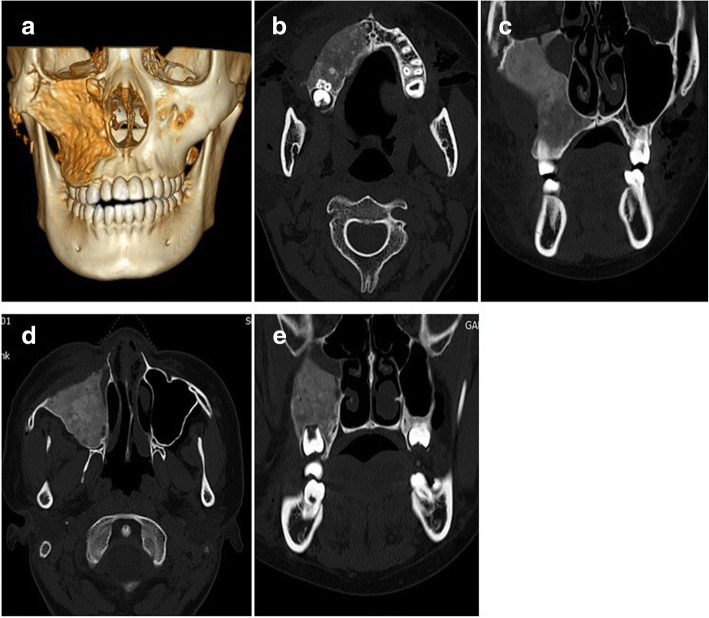

Fig. 6.

Postoperative radiographic images. a Postoperative 3D CT image showed relatively symmetrical skeletal contours and cortical bone formation on surgical site. b, d Four-month postoperative axial CT showed the restoration of the anterior protrusion of the maxilla. c, e Four-month postoperative coronal CT showed the improved contour of the right maxilla